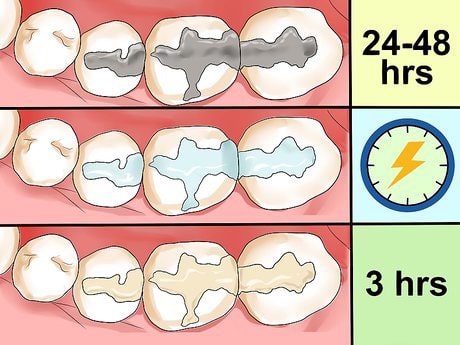

بسته به نوع پرکردگی که دریافت کردهاید، لازم است بلافاصله پس از انجام درمان در مورد غذا خوردن و نوشیدن احتیاط کنید.

- در پر کردن دندان با مواد کامپوزیتی (Resin Composite)، مادهی پرکننده با استفاده از نور فرابنفش بهسرعت سفت میشود، بنابراین معمولاً میتوانید خیلی زود پس از درمان غذا بخورید یا نوشیدنی بنوشید.با این حال، باید صبر کنید تا اثر بیحسی از بین برود، زیرا در غیر این صورت ممکن است ناخودآگاه لب، زبان یا گونه تان را گاز بگیرید.

- در پرکردگی دندان با آمالگام نقرهای (Silver Amalgam)، زمان بیشتری برای سخت شدن ماده نیاز است.بنابراین معمولاً توصیه میشود تا ۲۴ ساعت پس از درمان از خوردن غذاهای سفت خودداری کنید. در این مدت میتوانید از غذاهای نرم و آسانجَویدنی استفاده کنید، اما باید از خوراکی های ترد، سفت یا چسبنده پرهیز نمایید.

در پرکردگیهای کامپوزیتی بلافاصله پس از رفع بیحسی، اما در آمالگام حداقل ۲۴ ساعت بعد.